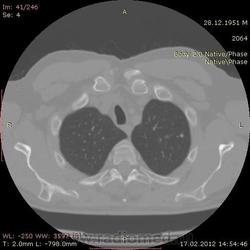

КТ.

В феврале 2012 года при очередном флюрографическом обследовании были обнаружены изменения в лёгких. По собственной инициативе было сделано КТ лёгких.